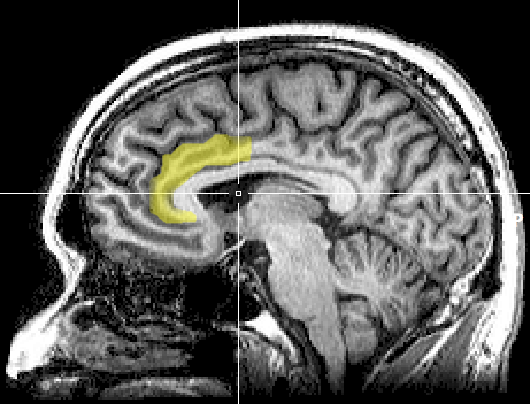

Der anteriore cinguläre Cortex (ACC). (Bild: Geoff B Hall, CC0)

Die Arbeitsweise des Systems ähnelt der des Gehirns: Ein Teil identifiziert Aktivität in einer bestimmten Region, eine Schaltstelle verarbeitet die Information und stimuliert daraufhin einen anderen Bereich. Der Implantat-Prototyp besitzt ein Array von Elektroden im anterioren cingulären Cortex (ACC), also einem Teil der Großhirnrinde. Die Anordnung erkennt bestimmte elektrische Muster im ACC, die mit Schmerzempfindung verbunden sind. Ein implantierter Chip übernimmt die Aufgabe der Schaltstelle: Er wertet die Signale aus und reagiert. Wenn er Schmerz erkennt, aktiviert er eine Stimulation des prälimbischen präfrontalen Cortex (PFC). Versuche hatten gezeigt, dass das den Schmerz dämpft. Diese Abfolge passiert so schnell, dass die Mediziner von „Echtzeit“ sprechen. Dieses System könnte in Zukunft besonders chronischen Schmerzpatienten helfen, die bereits unempfindlich auf die Behandlung mit herkömmlichen Schmerzmitteln reagieren. Die Erkenntnisse stellen zwar einen Durchbruch dar, die Technologie steht jedoch erst am Anfang und wurde bisher nur an Nagetieren getestet.

Einen „Eingangsarm zur Signalerkennung“ hatten sie nun schon: den ACC, der nachweislich Schmerzen bei Mensch und Tier verarbeitet. Nun mussten sie sich für den „Ausgangsarm zur Behandlung“ entscheiden. Früheren Studien hatten gezeigt, dass die Stimulation von PFC-Neuronen Schmerzsignale aus dem ACC lindern kann. Wenn der ACC ein weinendes Kind darstellt, das sich den Zeh gestoßen hat, ist der PFC das Elternteil, das darüber hinwegtröstet. Die Behandlung fand über eine optische Faser statt, die PFC-Neuronen stimuliert. Die Glasfaser nutzt Optogenetik, eine Methode, die Licht zur Steuerung genetisch veränderter Neuronen einsetzt. Zusammen stellt das System eine Echtzeit-Rückkopplungschleife dar, die Schmerz unterdrückt, sobald er auftaucht. Ein großer Vorteil dabei liegt darin, dass die PFC-Stimulation keine Euphorie hervorruft, wie etwa Opioide, und damit die Abhängigkeitswahrscheinlichkeit senkt. Durch die punktuelle Linderung gewöhnt sich das Gehirn auch nicht so leicht daran, ein Gewöhnungseffekt wird also unwahrscheinlicher.

Auf der anderen Seite liegt noch ein langer Weg vor einem Einsatz beim Menschen. Der ACC sei ein Hauptbahnhof für allerlei Empfindungen und habe weitreichende Verbindungen in andere Hirnregionen. Neben der Schmerzverarbeitung werden ihm Funktionen wie Empathie, Entscheidungsfindung und soziales Verhalten zugesprochen. „Da wir derzeit keine spezifischen anatomischen Ziele für die Schmerzbehandlung haben, werden die meisten Hirnregionen […] unweigerlich unspezifische Effekte haben“, so die Autoren.